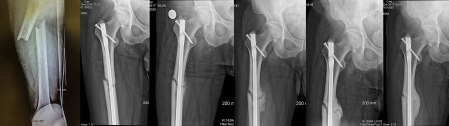

It’s been one year since I broke my femur – you can see the progress of my healing in this image:

I’m 95% healed, back on all my daily activities (including yoga!). The ortho doc said that if I have any trouble doing anything, I should just try harder!

I was in the ER in Santa Fe by 6:00PM – they did surgery ASAP: aligned the bones, drilled out the core, and installed an internal continuous rod, screwed everything together and stapled me up! I was in my room by 3AM.